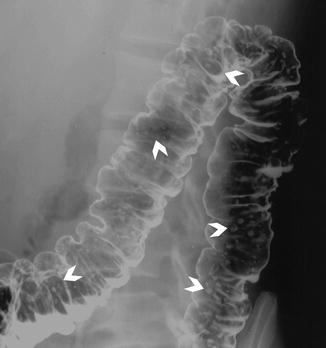

Crohns Disease X-Ray This lower abdominal X-ray shows narrowing stenosis of the end of the small intestine ileumwith loss of mucosal pattern and bowel wall thickening. However CD may also have extraintestinal manifestations which occur in at least 25 of CD patients. Crohns disease CD is a granulomatous systemic disorder of unknown etiology commonly involving the gastrointestinal tract.

This lower abdominal x-ray shows narrowing stenosis of the end of the small intestine ileum caused by Crohn disease. One of the most common is an abdominal X-ray. The role of cross-sectional imaging in the diagnosis of Crohn disease has expanded with recent technologic advances in computed tomography CT and magnetic resonance MR imaging that allow rapid acquisition of high-resolution images of the intestines.

When it passed into the small intestines this x-ray was taken lower GI series.

A solution containing a dye barium was swallowed by the patient. When it passed into the small intestines this x-ray was taken lower GI series. Imaging can help direct therapy and can predict important patient outcomes. Crohns disease typically affects the small intestine. Crohns disease typically affects the small intestine. Imaging the gut provides information on Crohns disease activity identifies complications and provides insight into patient symptoms. Crohn disease typically affects the small intestine whereas ulcerative colitis typically affects the large intestine.